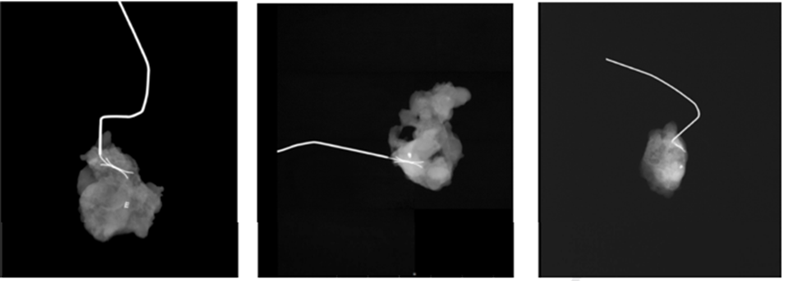

组1患者(n=22)接受SLNB,至少取样3个淋巴结。组2的患者(n=25)在NACT前用金属标记物(Marker)标记出现转移的腋窝淋巴结,SLNB前一天或当天通过超声引导下导丝定位Marker标记的淋巴结,在标准SLNB之外,至少再取样3个淋巴结。两组患者均采用专利蓝V染色和Tc99同位素标记,以最大限度提高淋巴结检出率。术中影像学证实Marker标记的淋巴结被成功切除(图1)。

图1. 术中X线检查显示Marker标记的淋巴结